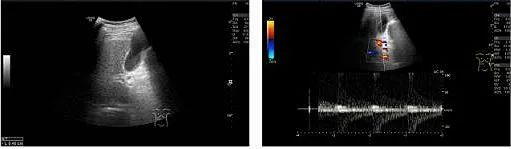

1)超聲復查

TIPS術(shù)后:

? 支架內(nèi)血流充填好,支架內(nèi)峰值流速206cm/s

? 門靜脈主干內(nèi)徑12mm,門靜脈血流信號充填良好,為單色向肝血流,PSV 72cm/s

? 脾靜脈胰腺段內(nèi)徑9mm,PSV 37cm/s,脾門處內(nèi)徑10mm,PSV 36cm/s

? 腸系膜上靜脈近匯合處內(nèi)徑9mm,PSV 41cm/s